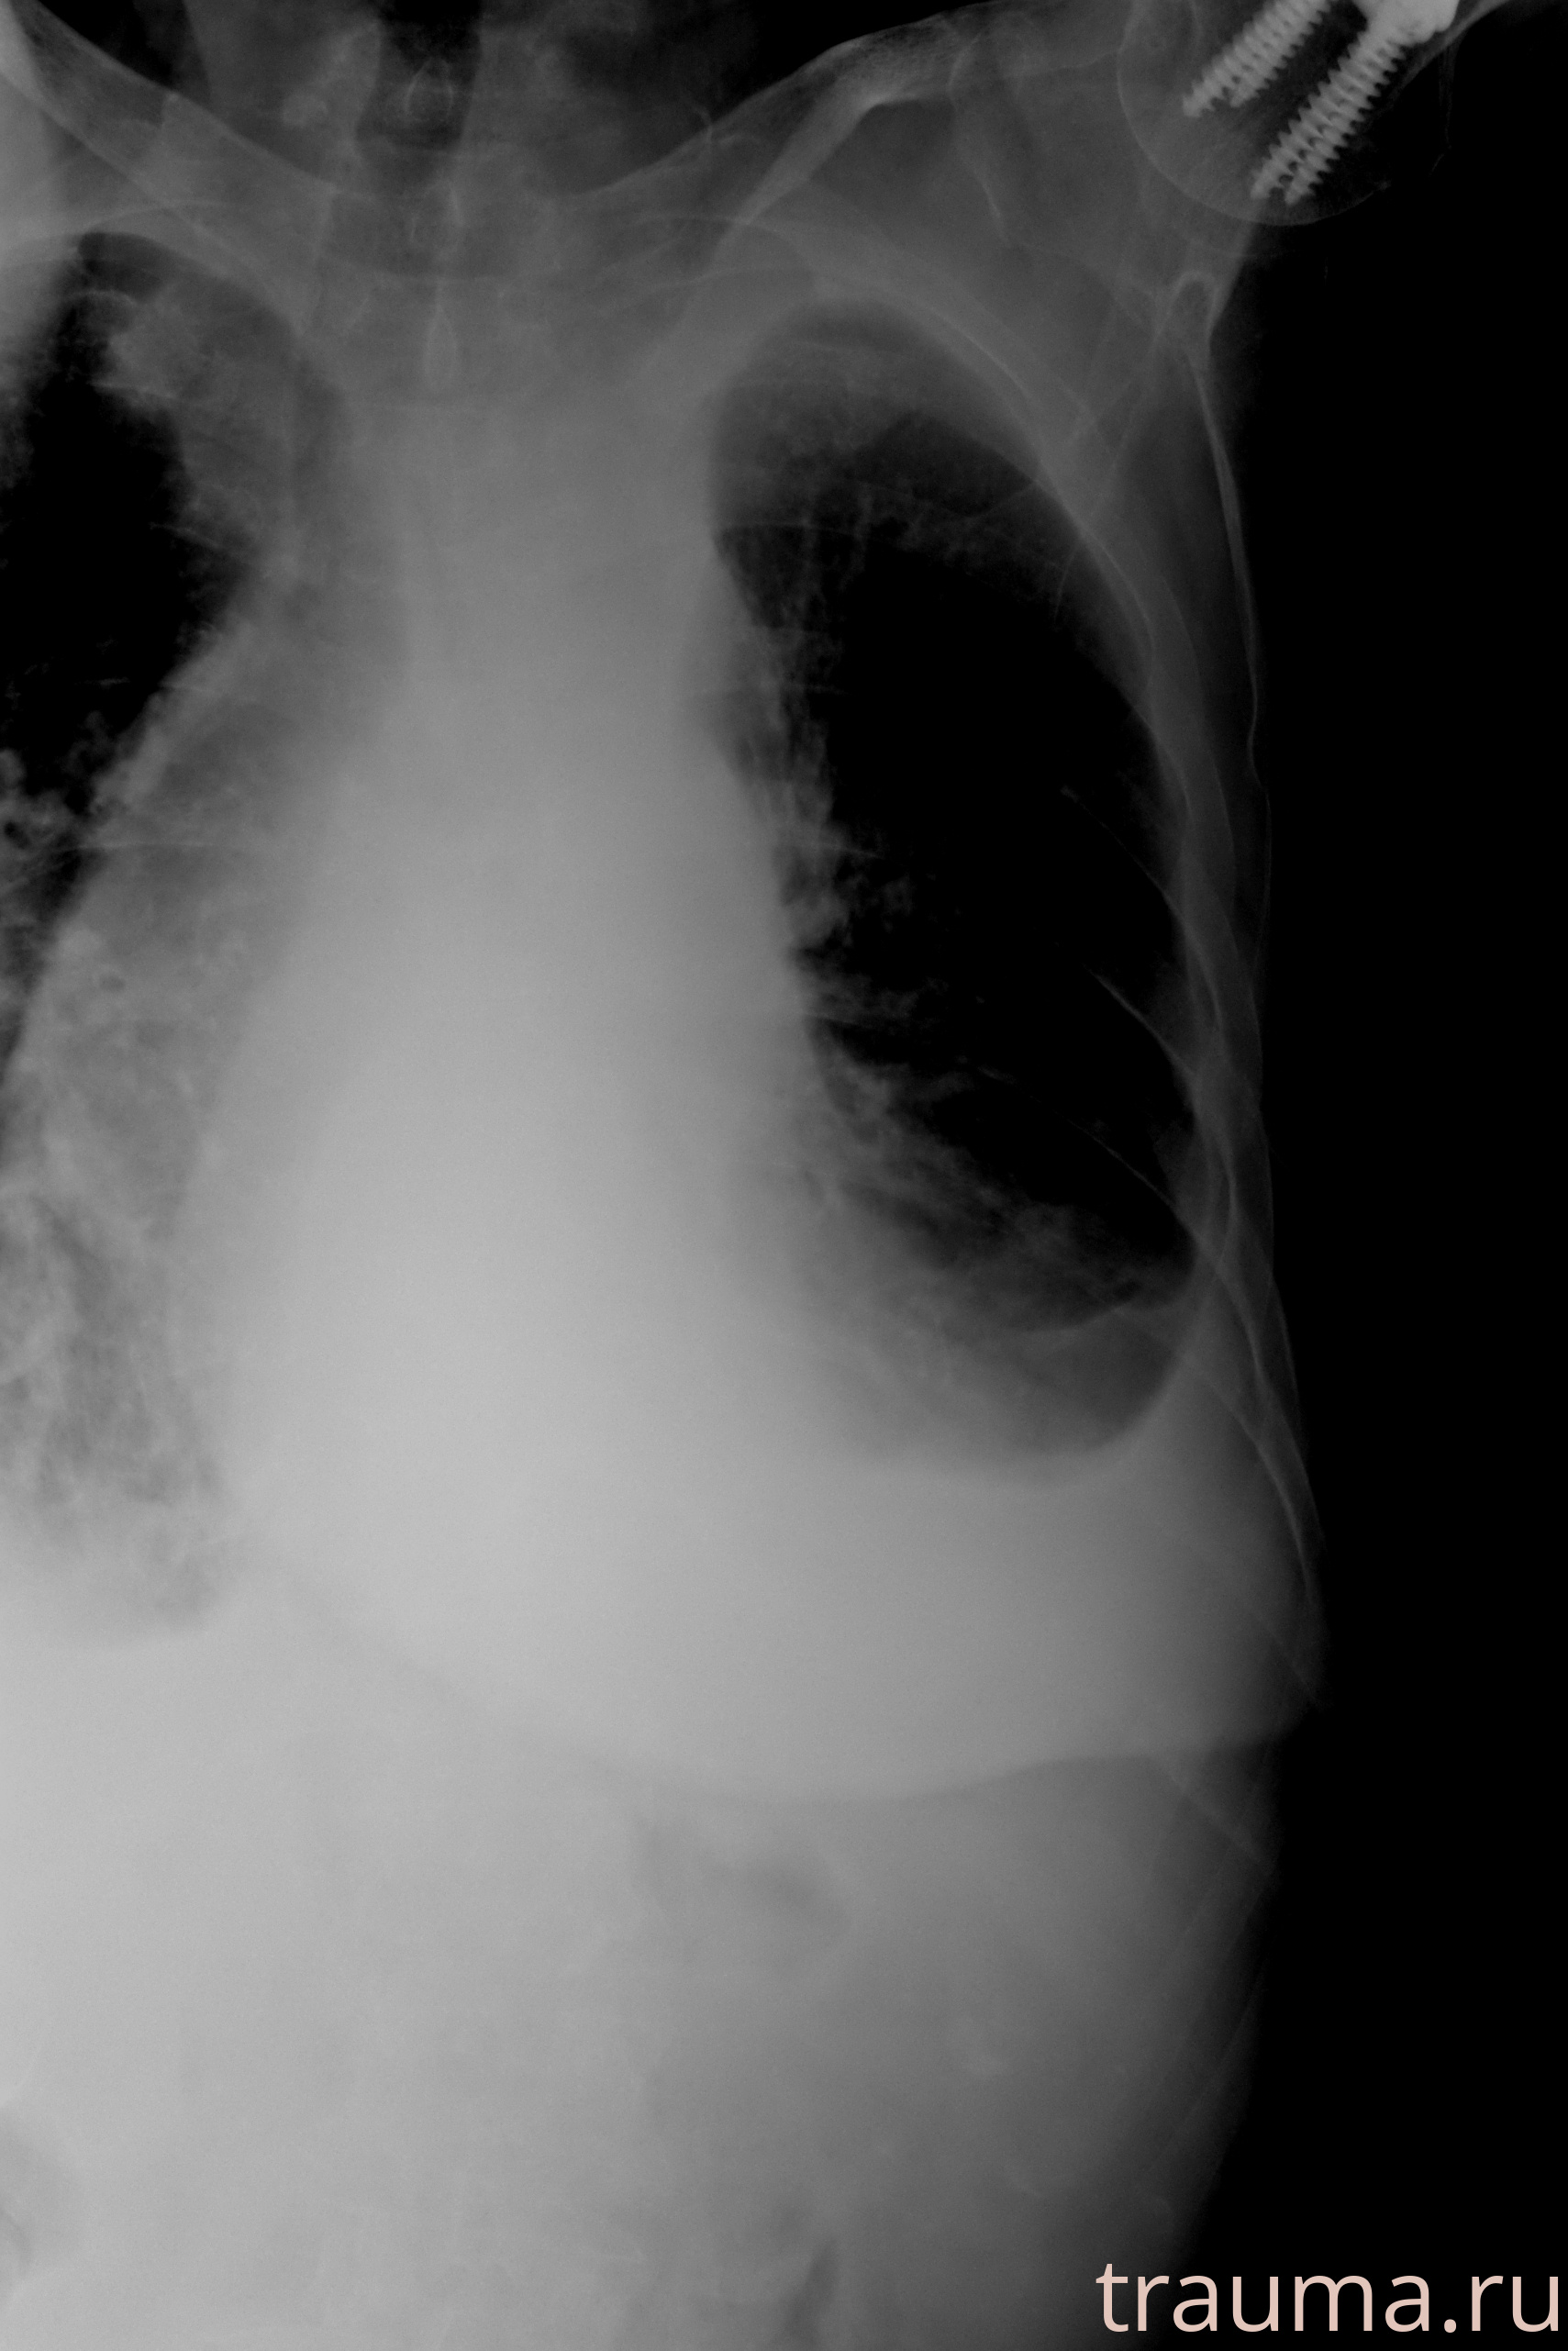

Рентген на дому: по вашему адресу приезжает врач-рентгенолог, травматолог-ортопед с мобильным рентгеновским аппаратом, проводит диагностику травмы или заболевания, делает необходимые рентгенограммы, дает рекомендации по дальнейшему лечению. Получить качественные снимки в домашних условиях возможно благодаря уникальной методике, разработанной МосРентген Центром для института  Склифосовского

при переломе шейки бедра и пневмонии от компании МосРентген Центр - партнера Института имени Склифосовского